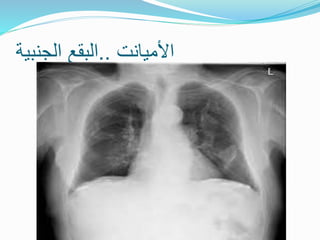

‫األميانت‬ ‫لداء‬ ‫الشعاعية‬ ‫العالمات‬



‫بقع‬

‫جنبية‬

‫متسمكة‬

‫الوريقة‬ ‫على‬ ‫متكلسة‬ ‫أو‬

‫الجدارية‬

‫للجنب‬

‫الرئتين‬ ‫من‬ ‫السفلية‬ ‫لألقسام‬ ‫المغلفة‬ ‫خاصة‬ ‫و‬

‫و‬

‫الحاجز‬ ‫للحجاب‬



‫الجانب‬ ‫ثنائي‬ ً‫ا‬‫غالب‬ ‫حميد‬ ‫جنب‬ ‫انصباب‬

‫منتشر‬ ‫رئوي‬ ‫تليف‬

‫رئوي‬ ‫انخماص‬

.

‫األميانت‬ ‫لداء‬ ‫الشعاعية‬‫العالمات‬  ‫بقع‬ ‫جنبية‬ ‫متسمكة‬ ‫الوريقة‬ ‫على‬ ‫متكلسة‬ ‫أو‬ ‫الجدارية‬ ‫للجنب‬ ‫الرئتين‬ ‫من‬ ‫السفلية‬ ‫لألقسام‬ ‫المغلفة‬ ‫خاصة‬ ‫و‬ ‫و‬ ‫الحاجز‬ ‫للحجاب‬  ‫الجانب‬ ‫ثنائي‬ ً‫ا‬‫غالب‬ ‫حميد‬ ‫جنب‬ ‫انصباب‬  ‫منتشر‬ ‫رئوي‬ ‫تليف‬  ‫رئوي‬ ‫انخماص‬ .